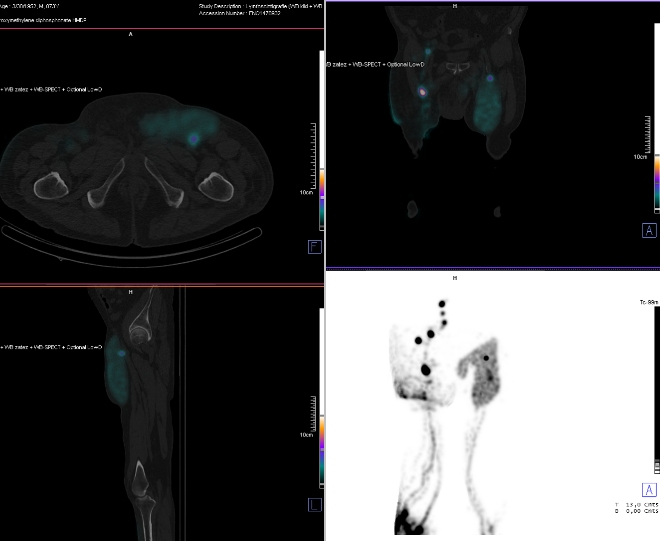

/ Obr. č. 2: SPECT/CT /

Po klidu nejsou vůbec patrné kolektory, radioindikátor je pouze v místě vpichů.

Po zátěži zobrazeny kolektory na bércích a stehně, je výrazný reflux do podkoží pravého bérce, proximální části levého stehna, méně výrazně i proximální části pravého stehna (což potvrzuje i SPECT/C). Na levém bérci štěpení kolektoru, na pravém stehně výrazné štěpení kolektorů, všechny probíhají povrchovou cestou – nezasahují do hlubokého systému. V levém třísle v oblasti refluxu je dle SPECT/CT patrná ojedinělá tříselná uzlina, vpravo zobrazeny tři tříselné uzliny a tři uzliny iliakální.

Těžce patologický nález - výrazné funkční a anatomické změny lymfatického systému dolních končetin, jistě v důsledku operačního výkonu